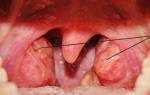

Характерным признаком данной клинической формы является увеличение и гиперемия небных миндалин, на поверхности которых располагаются небольшие фолликулы, которые при разрыве образуют язвочки.

Лакунарная ангина — клиническая форма ангины, характеризующаяся выраженной разлитой гиперемией миндалин, нередко отёчностью нёбных дужек, слизисто-гнойным экссудатом на поверхности миндалин, умеренной реакцией регионарных лимфатических узлов. Обычно длительность заболевания составляет 10 дней.

Симптомы лакунарной ангины: небные миндалины краснеют, увеличиваются в размере, при надавливании на них из лакун выделяется гной, а через несколько дней от начала процесса гнойные массы видны невооруженным глазом на поверхности миндалин. Голос пациента становится гнусавым, а изо рта появляется неприятный запах.